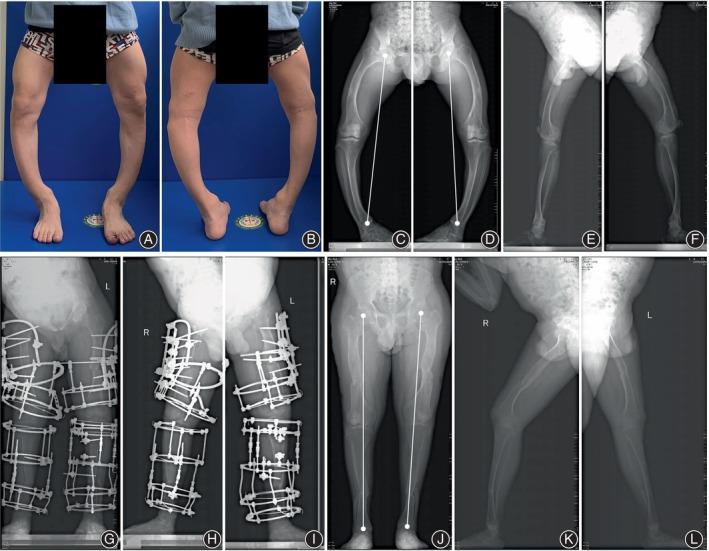

The management of femoral multiplanar deformity remains a great challenge for orthopaedic surgeons. The focal dome osteotomy (FDO) combined with Ilizarov technique is a theoretically ideal method for treating femoral multiplanar deformity, but the clinical evidence is limited. The aim of this study is to assess the clinical and radiological outcomes of this combined strategy for correcting femoral multiplanar deformities.

A retrospective analysis was conducted to analyze 20 patients (29 limbs) with femoral multiplanar deformities treated by FDO combined with Ilizarov external fixation in our limb deformity center between 2017 and 2022. Preoperative and postoperative radiographical parameters were measured, including lateral proximal femoral angle (LPFA), mechanical lateral distal femoral angle (mLDFA), middle diaphysis angle (MDA), anatomic posterior distal femoral angle (aPDFA), mechanical axis deviation (MAD), and limb length discrepancy (LLD). Clinical assessments included a self-made questionnaire for exercise capacity score (ECS), visual analog scale (VAS), and the 36-Item Short-Form Health Survey (SF-36) score.

There were eight males and 12 females, with a mean age of 32.8 years (14-61 years). All patients completed follow-up with a mean follow-up duration of 41.5 (27-81) months. The mean EFT was 8.9 (1.4-20.2) months. At final follow-up, significantly improvement was noted regarding mean LLD (from 1.8 to 0.4 cm, p < 0.05), MDA (from 31.8° to 10.4°, p < 0.05), aPDFA (from 97.6° to 91.8°, p < 0.05), MAD (from 22.4 to 5.3 mm, p < 0.05), CORA on the true deformity plane (from 32.4° to 6.8°, p < 0.05). The mean VAS was decreased from 4.03 (2.0-6.0) preoperatively to 1.38 (0-3.0) at final follow-up (p < 0.05). The mean score of each item of SF-36 was significantly improved at final follow-up (p < 0.05). The mean ECS was improved from 8.2 (5-12) preoperatively to 11.4 (8-13) at final follow-up (p < 0.05). During the follow-up, one patient underwent pin exchange. One patient underwent internal fixation to replace the Ilizarov fixation 1.4 months after the first surgery. Residual LLD (>0.5 cm) was noted in four patients but without significant symptoms. No serious complications occurred.

The strategy of FDO combined with Ilizarov fixation could provide powerful ability and good flexibility for correcting femoral multiplanar deformities without significant complications.